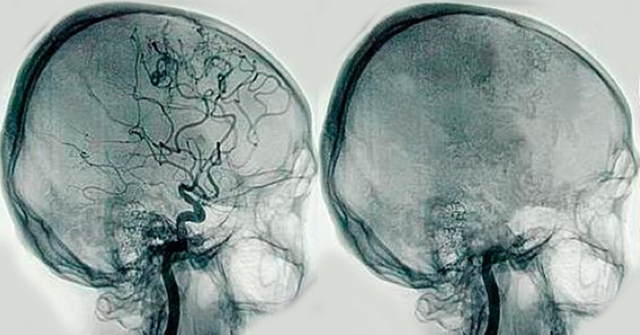

• Angiografia

Angiografia

-Inventor: Antonio Caetan de Abreu.

-es el estudio de los vasos sanguíneos que no son visibles mediante la radiología convencional.

-se crea la Angeografia digital

-se crea la Angiografia con substraccion digital y reconstruccion digital